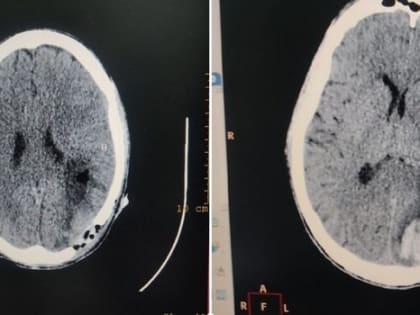

В Серпуховскую областную больницу доставили пациента с серьезной травмой мозга

Мужчина в возрасте 33 лет пожаловался на то, что у него в течении трех дней ухудшается зрение.